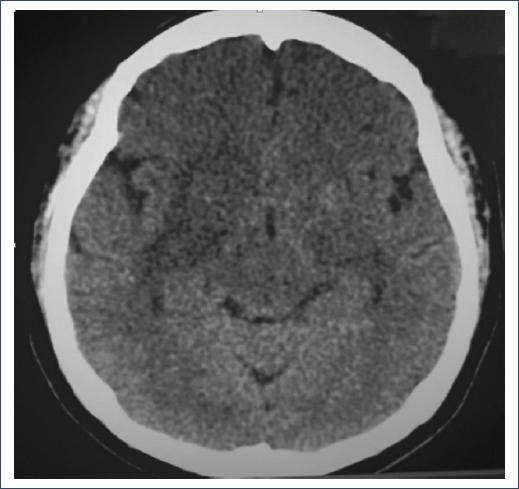

GCS 15 points: bilateral pupillary diameter 3 mm, brainstem reflexes and no cranial nerve alterations, unaltered motor sensitivity and response, and preserved mental functions. Grade III osteotendinous reflexes. She received neurocritical care on the recommendation of the neurology service, remained under deep sedation after cesarean section for 48 h, with ICP monitoring inferred by optic nerve sheaths diameter measurement ICP 10-12 mmHg, and subsequently emerged with delirium treated with haloperidol 5 mg every 6 h for 7 days without any other manifestation of neurological deterioration. Tomography: hypodensities in corticosubcortical areas in the biparietal region, as well as hypodense images of the superior longitudinal sinus, which makes the diagnosis of venous sinus thrombosis highly suggestive (Fig. 3).

SUMMARY OF CLINICAL EVOLUTION